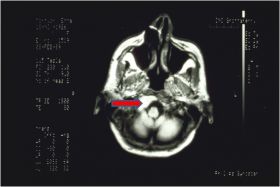

[[File:Capsaicina.jpg|right|280px]] | |||

Questo caso mostra in modo concreto perché il numero clinico non può essere trattato come un valore assoluto. | |||

Una paziente (circa 60 anni) riferisce dolore orofacciale diffuso bilaterale (temporali e occipitale) associato a bruciore della bocca (BMS) da oltre 10 anni, spesso notturno, con peggioramento riferito dopo alimentazione piccante. | |||

Non vengono rilevate discrepanze occlusali significative; una placca notturna risulta inefficace. In precedenza la paziente era stata interpretata come affetta da dolore orofacciale atipico (AOP) a possibile componente psicosomatica e successivamente come affetta da disordini temporomandibolari (TMD) secondo protocolli standardizzati. | |||

'''Sᵢ (stato del sistema):''' | |||

il sistema è clinicamente positivo (dolore persistente), ma i parametri quantitativi disponibili nei contesti specialistici non evidenziano anomalie strutturali o funzionali macroscopiche. | |||

'''Cᵢ (contesto):''' | |||

* in contesto odontoiatrico vengono eseguiti test gnatologici (assiografia ed EMG interferenziale) con referti di apparente normalità; | |||

* in contesto neurofisiologico vengono eseguiti test trigeminali (riflessi e potenziali evocati) che restituiscono, ancora, una apparente normalità. | |||

'''Oᵢ (ordine osservativo):''' | |||

la sequenza delle osservazioni conduce a una stabilità numerica che produce una falsa rassicurazione clinica: contesti differenti convergono verso valori compatibili con la norma, mentre la sintomatologia dolorosa persiste. | |||

Quando la procedura diagnostica giunge a un punto di azzeramento del potere discriminativo dei test (demarcatore di coerenza <math>\tau</math> di fatto nullo), diventa obbligatorio ampliare l’osservazione. | |||

La risonanza magnetica dell’encefalo evidenzia una lesione neoplastica del tronco encefalico (neurinoma) con coinvolgimento della regione del forame occipitale. | |||

Questo caso rappresenta un falso negativo strutturale della diagnostica scalare: il numero resta “normale” mentre lo stato clinico è patologico. | |||